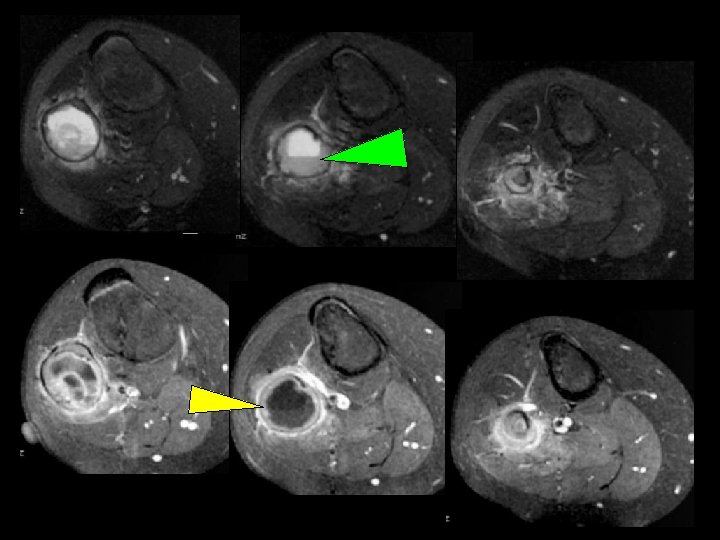

tumeurs à cellules géantes

tumeurs à cellules géantes -tumeur à myéloplaxes; ostéoclastome -frontière bénignité / malignité : faite de cellules stromales mononucléées et de cellules géantes multinucléées -fréquente : 21% des T osseuses bénignes -adulte jeune après soudure de la plaque de croissance après 20 ans , début de la 3ème décennie ++++ (par opposition avec le KOA (2ème décennie) -siège : 85% épiphyse des os longs (membres inférieurs +++) : prés du genou / loin du coude

- lacune métaphysoépiphysaire excentrée avec cloisons de refend - souffle la corticale - si maligne : rupture corticale, réaction périostée spiculaire, éperon de Codman, parties molles